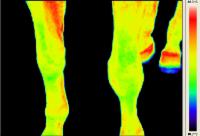

Rasmus - Pferd mit Arthrose - Horse with Osteoarthritis